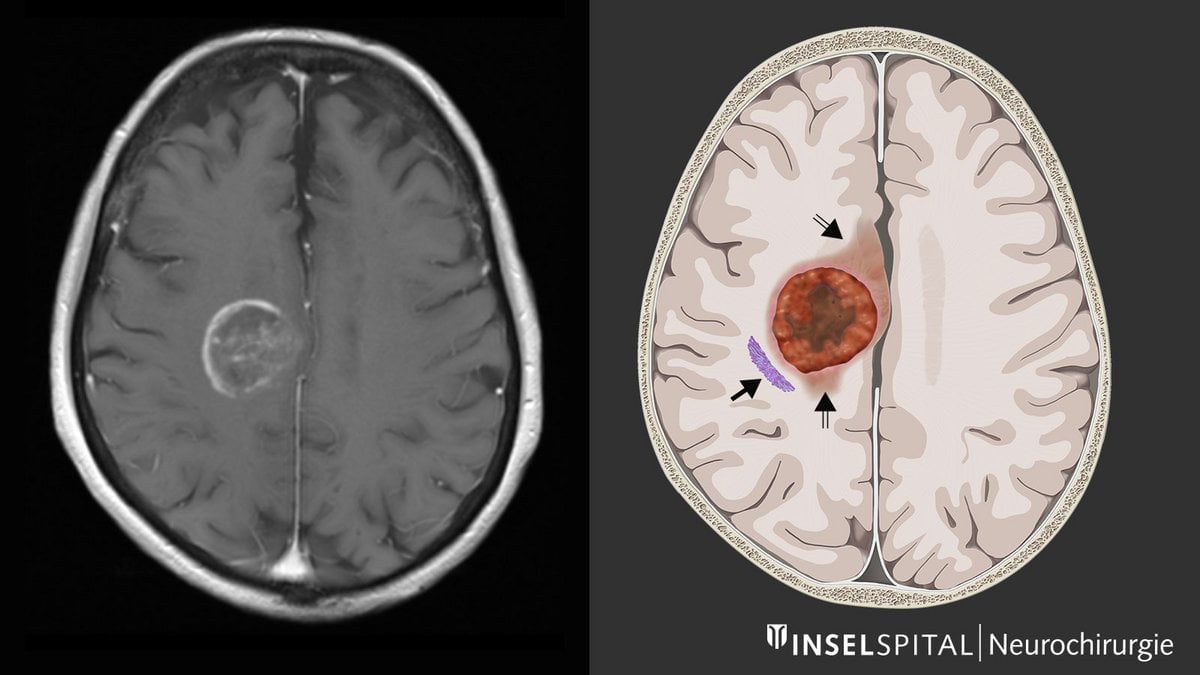

Des chercheurs de l’université du Michigan viennent de réaliser une importante découverte concernant le glioblastome, un cancer du cerveau aussi redouté que difficile à traiter.

Malgré les avancées de la chirurgie, de la radiothérapie et de la chimiothéraie, l’espérance de vie de ce cancer dépasse rarement deux ans après un diagnostic. Face à cette impasse, les scientifiques ont tenté une approche radicale : affamer la tumeur.

Dans un cerveau sain, les acides aminés servent de carburant pour assurer le bon fonctionnement des cellules. Mais chez les patients atteints de glioblastome, la tumeur détourne ces nutriments pour se multiplier. L’idée des chercheurs a donc été de priver la tumeur d’une partie de ces briques essentielles, afin de vérifier si sa croissance pouvait être freinée.

Les expériences ont été menées sur des souris atteintes de glioblastome, et les résultats ont dépassé les attentes. « Nous avons modifié l’alimentation dans les modèles murins et nous avons pu ralentir de manière significative et bloquer la croissance de ces tumeurs », a expliqué le Dr Daniel Wahl, oncologue à l’université du Michigan.

L’équipe s’est particulièrement concentrée sur deux acides aminés : la sérine et la glycine. Leur suppression a transformé la réponse des tumeurs aux traitements classiques. « Quand nous avons supprimé les acides aminés sérine et glycine chez les souris, leur réponse à la radiothérapie et à la chimiothérapie étaient meilleure et les tumeurs étaient plus petites que chez les souris témoins nourries avec de la sérine », a indiqué le Dr Deepak Nagrath, dans Science Daily. Cette stratégie, qui consiste à exploiter une faiblesse du métabolisme tumoral, pourrait bien marquer un tournant. En privant les cellules cancéreuses d’éléments essentiels à leur croissance,les chercheurs sont parvenus à les rendre plus vulnérables aux traitements existants. Une approche qui ouvre la voie à de nouvelles thérapies combinant régime alimentaire ciblé et protocoles médicaux.

Pour l’heure, cette découverte n’a été validée qu’en laboratoire mais l’équipe scientifique nourrit de grands espoirs/ »Nous pensons que cette vulnérabilité métabolique peur être exploitée et qu’elle pourrait changer la manière dont nous traitons ce cancer », ajoutent les chercheurs.

La prochaine étape est de vérifier su cette stratégie est applicable à l’humain. Des essais cliniques sont déjà envisagés afin de tester l’impact de régimes spécialement conçus pour réduire la sérine dans le sang. Si ces résultats se confirment, il s’agirait d’une avancée majeure dans la lutte contre l’un des cancers du cerveau les plus agressifs.